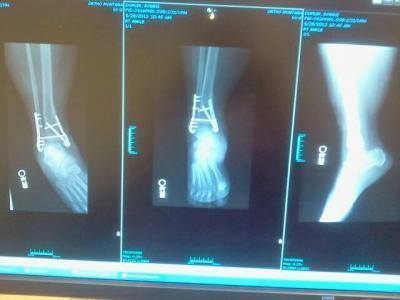

broke my right ankle. had to get pins and plates to hold it together :c